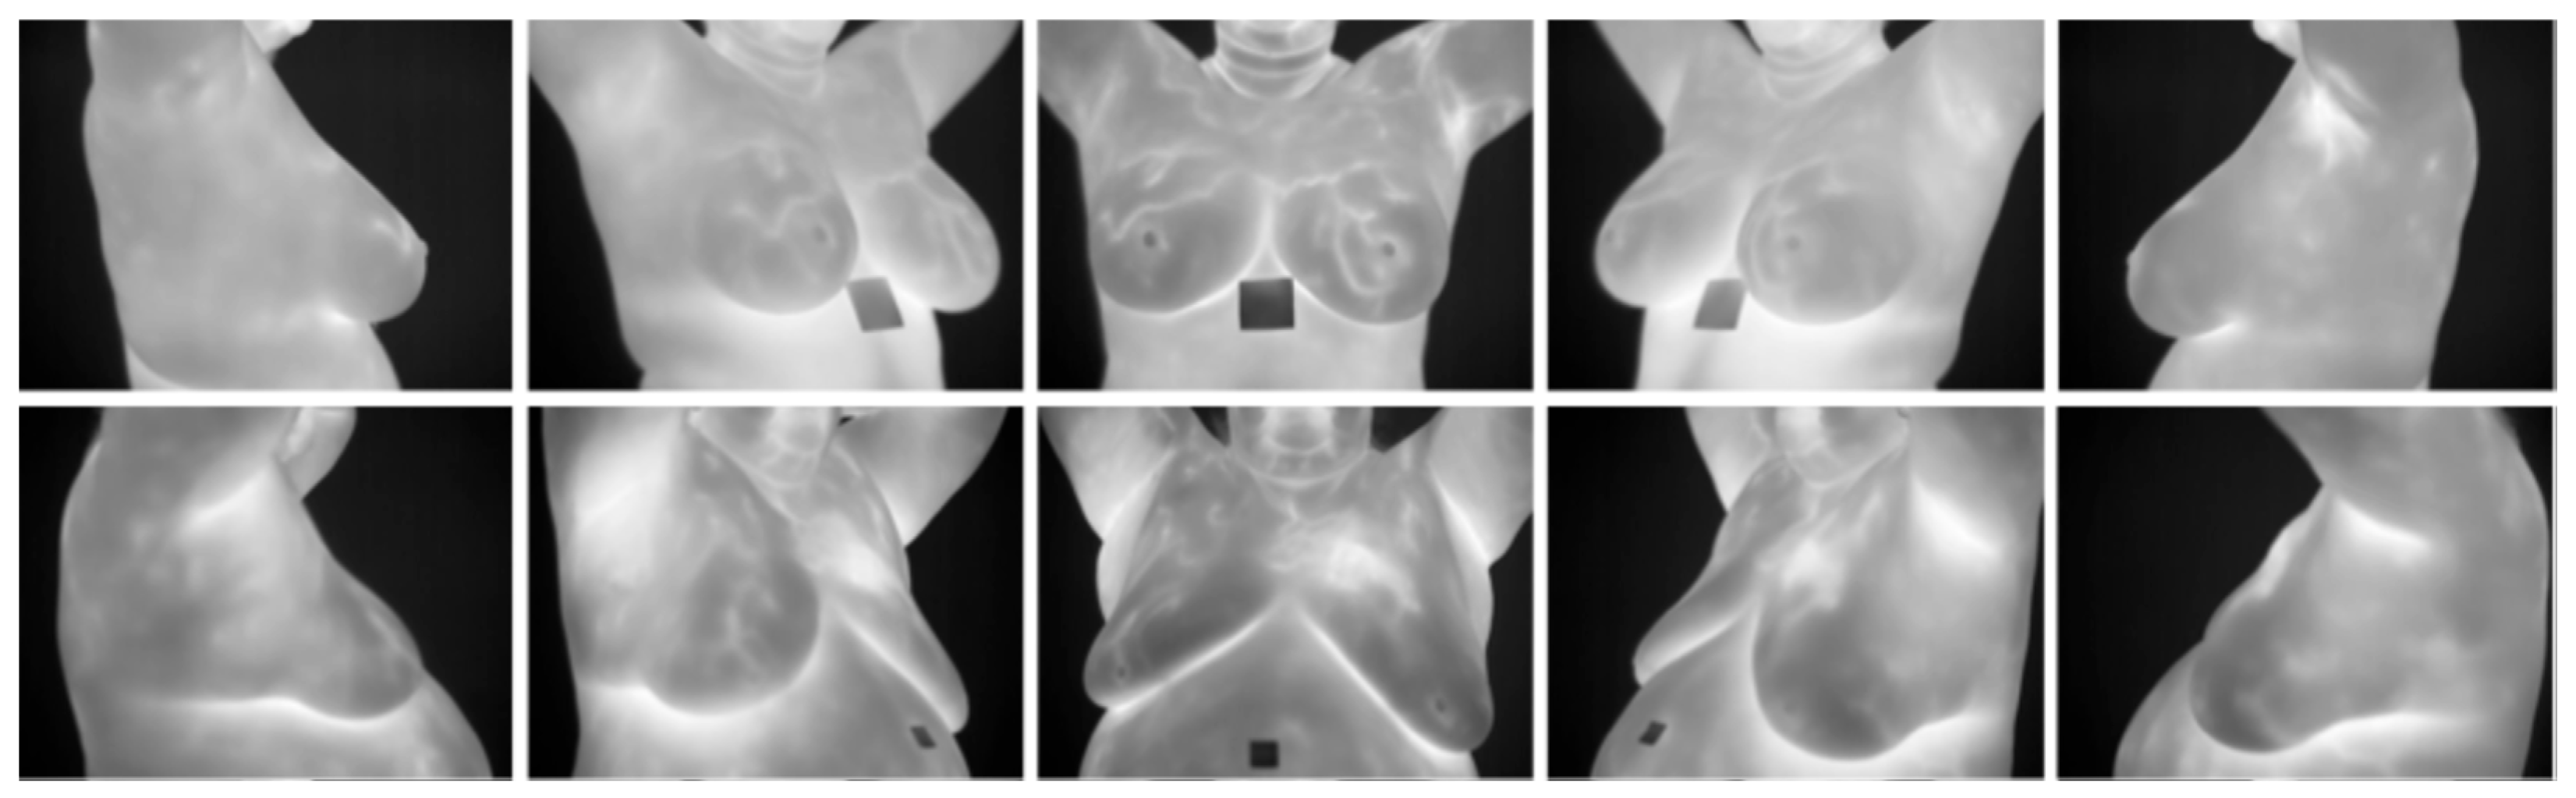

- DMR-IR Dataset: The Database for Mastology Research Infrared (DMR-IR) dataset [39] is the most widely used database in research studies. Of the 26 studies covered in this review, 20, 77%, used this dataset. The DMR-IR dataset includes infrared (IR) images, several digitized mammograms, several ROI masks, and clinical data for 293 patients captured at the Hospital Universitario Antonio Pedro (HUAP) of the Federal University Fluminense. The use of this dataset was approved by the Ethical Committee of the HUAP and registered with the Brazilian Ministry of Health under number CAAE: 01042812.0.0000.5243 and is publicly available at http://visual.ic.uff.br/dmi/, accessed on 6 April 2025. Infrared images are captured using Static Image Thermography (SIT) and Dynamic Image Thermography (DIT) described in [19]. The database also includes segmented images for 56 patients (37 sick and 19 normal). Figure 4 shows sample images from this dataset.